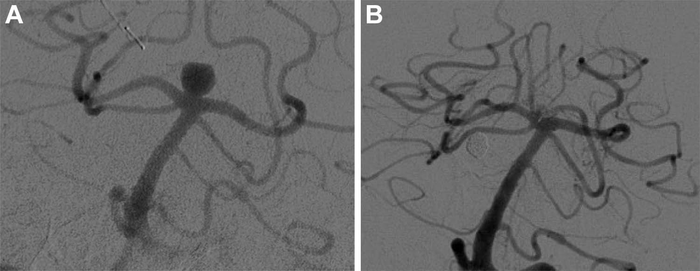

Digital subtraction angiography images show basilar tip aneurysm (A) before and (B) at last follow-up after Woven EndoBridge device placement. Image courtesy of Radiological Society of North America

A braided wire device known as the Woven EndoBridge (WEB) was developed to overcome those limitations. The device is placed inside the aneurysm under angiographic guidance, where it causes a clot to form, closing off the aneurysm and reducing the risk of bleeding without requiring supporting stents or blood thinners.